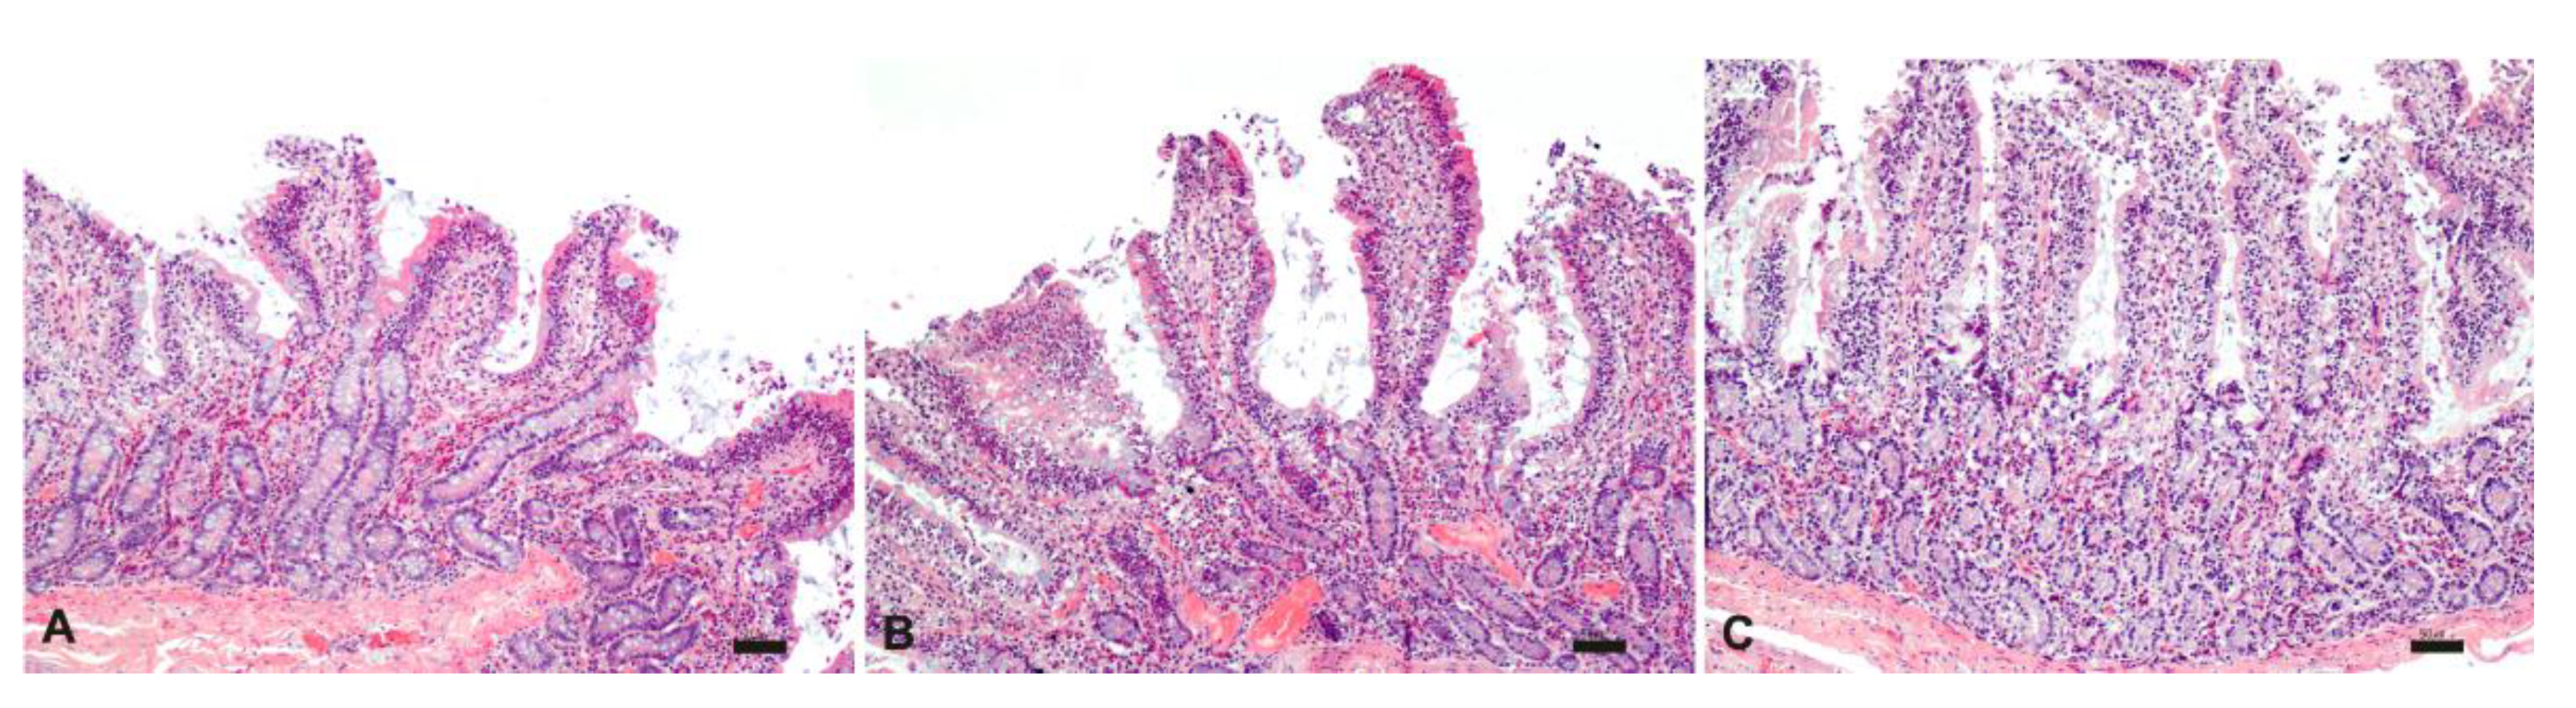

The histological analysis carried out on intestinal samples stored at 25°C was characterized by tissue and cell morphology, with similar features described at time zero and up to 3 h. Starting from 4 h, severe epithelial degeneration with multiple weakly eosinophilic intracytoplasmic vacuoles of varying sizes, multifocal plasma membrane discontinuities, and nuclear pyknosis were observed. Furthermore, the lamina propria, in addition to the described inflammatory infiltrate, was characterized by widespread edema and by numerous extravasated red blood cells (Figure 7).

Figure 7.

Histological evaluation of intestinal tissue stored at 25°C at 1 h (A), 2 h (B) and 3 h (C). HE; bar: 50 µm.

Unlike what was observed in the samples stored at room temperature, the samples stored at 37 °C were histologically characterized by diffuse morphological alterations starting from 2 h, indicating a lower stability of the intestine at higher temperatures (Figure 8).

Figure 8.

Histological evaluation of intestinal tissue stored at 37°C at 1 h (A), 2 h (B) and 3 h (C). HE; bar: 50 µm.